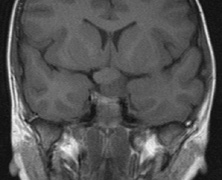

Intracranial leptomeningeal capillary vascular malformation (Figs. 21 and 22) is associated with seizures and contralateral neuromuscular weakness. Central nervous system involvement correlates highly with ipsilateral involvement of the V1 dermatome by a PWS.208,218

Fig. 22. Axial T2-weighted (a) and coronal T1-weighted (b) images of a 16-year-old boy with a port-wine lesion over the right side of his face. The right hemisphere is markedly atrophic and abnormal draining veins are seen within the right lateral ventricle (arrowheads). (c, d) The entire right hemisphere is covered by an enhancing pial angioma and the choroid plexi are enlarged. Enhancing retinal angiomas (arrows), typical of Sturge-Weber syndrome, are seen in (d).